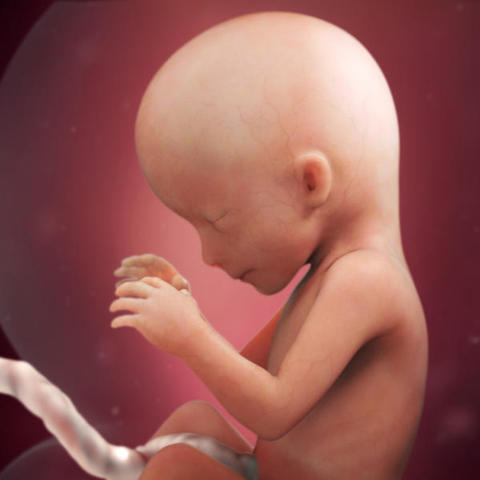

• Semana 11

Semana 11

Sus órganos, cerebro, pulmones, hígado, riñones e intestinos están formados y aumentan de volumen. Se ha formado el diafragma dividiendo el tronco del bebé en dos partes diferenciadas.

- La cabeza aun representa la mitad de su longitud total.

- Los rasgos faciales ya le hacen parecer una "personilla".

- El oído interno se habrá desarrollado por completo.

- Han empezado a formarse las cuerdas vocales de la laringe.